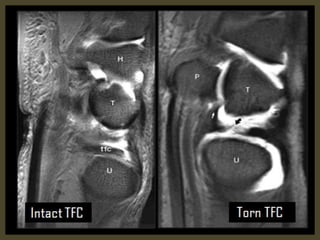

Triangular fibrocartilage complex tear.

Acute TFCC tear on FS T2-WI (A) and T1-WI (B).